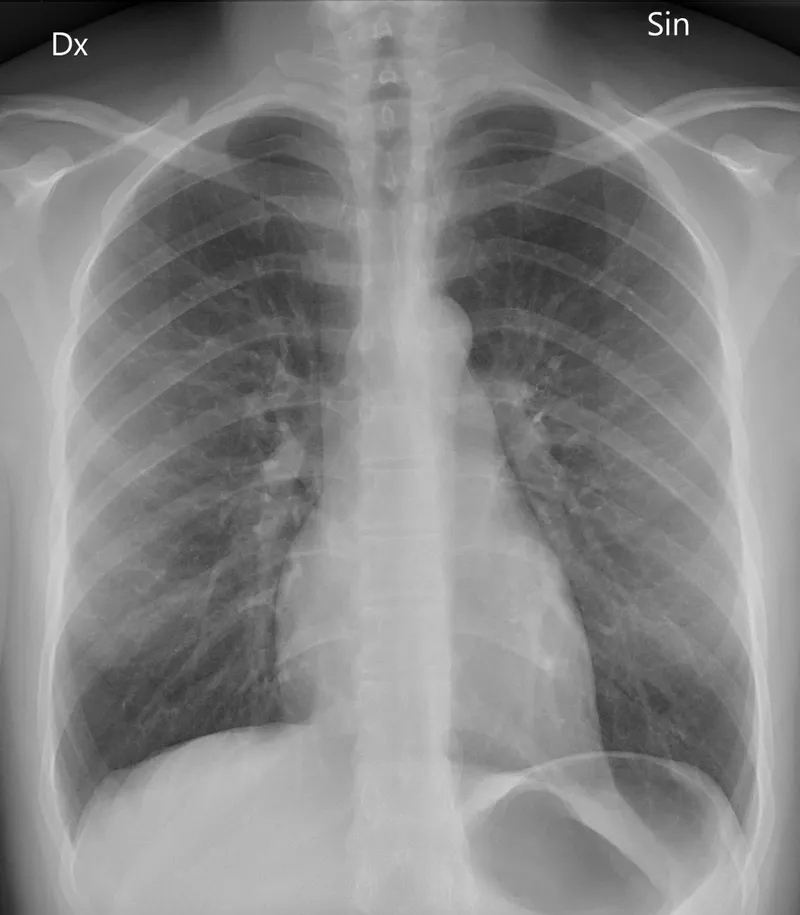

📌 Remember: ABCDEFGHI - Airway, Bones, Cardiac, Diaphragm, Effusion, Fields, Gastric, Hila, Implants - Systematic chest X-ray evaluation sequence

💡 Master This: The silhouette sign principle - loss of normal anatomical borders occurs only when pathology is anatomically contiguous with the structure, enabling precise lobar localization of pulmonary disease

⭐ Clinical Pearl: Hilar enlargement >3cm in diameter has >85% specificity for malignancy in patients over 40 years, requiring immediate CT evaluation for staging